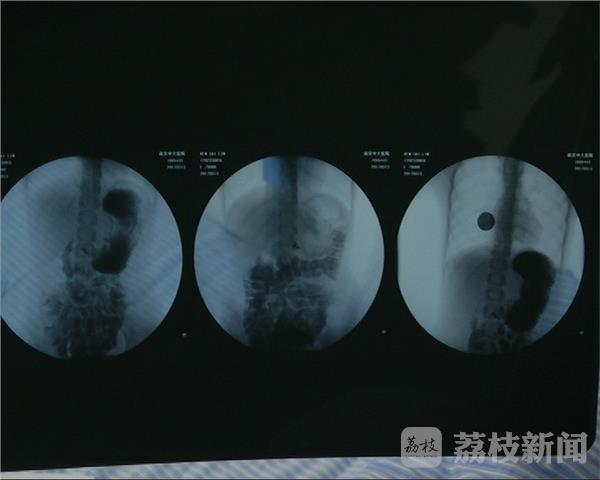

几经辗转,慧慧来到了南京。看到这样的病人,东南大学附属中大医院的医生们也犯了难,按照常规的检查,慧慧的身体确实没有大碍。为了找到病因,十多个学科的医生联合会诊,终于揪出了困扰这个女孩的元凶:胃排空障碍。正是这个原因,慧慧的胃消化能力还不到正常人的一半,进食后就会反酸、呕吐。

医生表示,胃排空障碍和很多病的症状相似,有时候医生也会混淆,因此找出病因很困难。经过微创手术,目前慧慧的病情有了很大好转。医生提醒,婴儿出生后呕吐、吐奶很正常,家长不必过于担心。但如果一直持续,常规检查又找不到病因,家长就要考虑'胃排空障碍'这样的少见病。